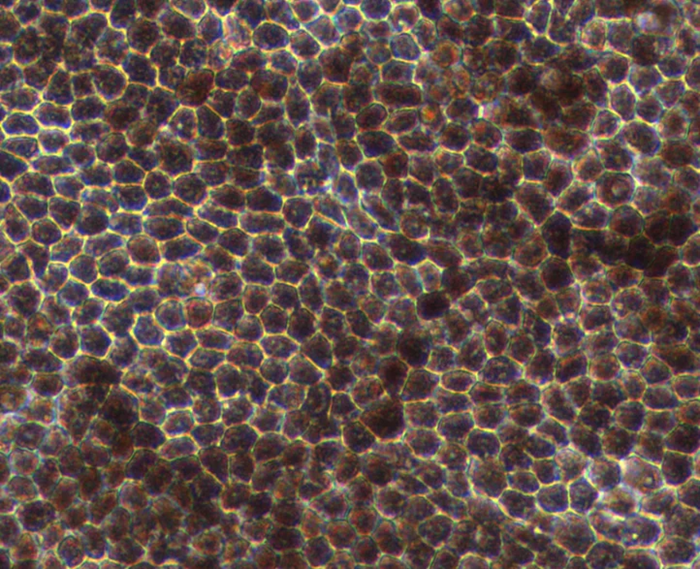

Human iPSCs forming a two-dimensional layer generate in vitro retinal pigment epithelial cells, which are pigmented and display typical cobblestone morphology.

Hexagonal morphology and pigmentation typically observed in mature RPE cells. Image Credit: Newcells Biotech

The in vitro model closely recapitulates crucial functions found in vivo, including tight barrier formation and photoreceptor outer segment phagocytosis.